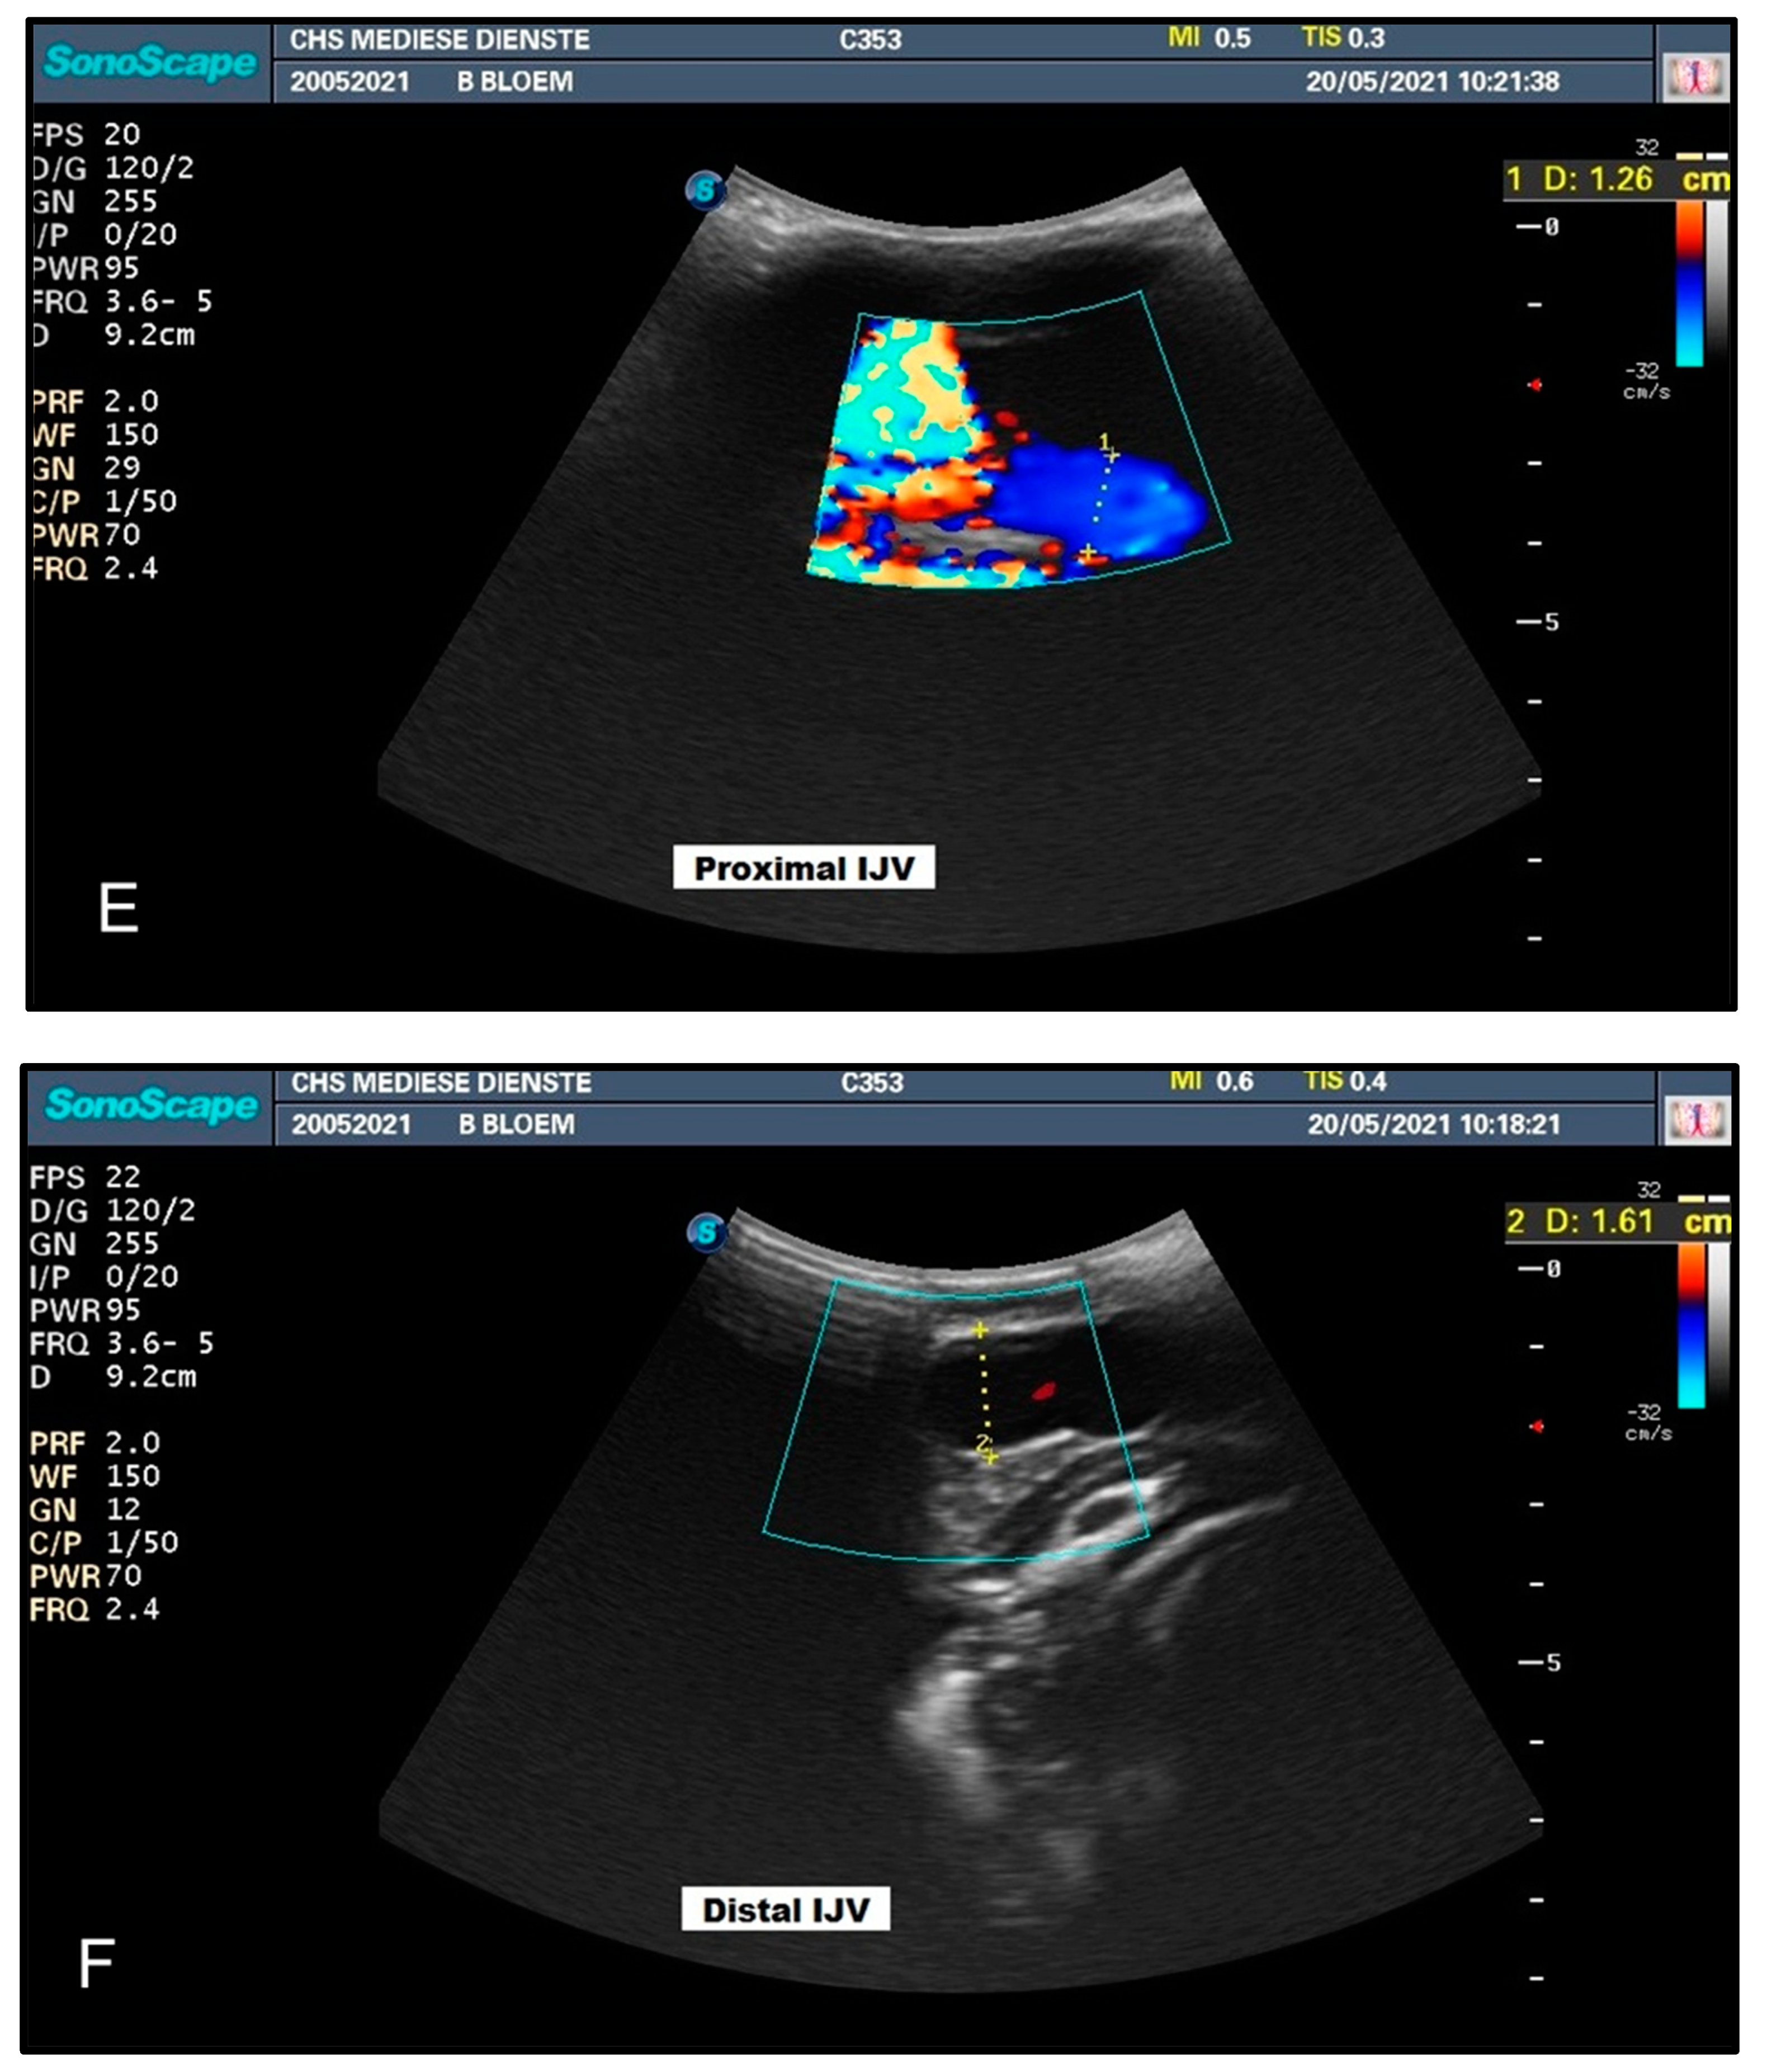

| Head Position | Diameter (mm) CCA | Diameter (mm) IJV | ||

|---|---|---|---|---|

| Proximal | Distal | Proximal | Distal | |

| Head Up | 13.8 | 13.9 | 4.6 | 13.9 |

| Head Down | 13.1 | 13.3 | 12.6 | 16.1 |